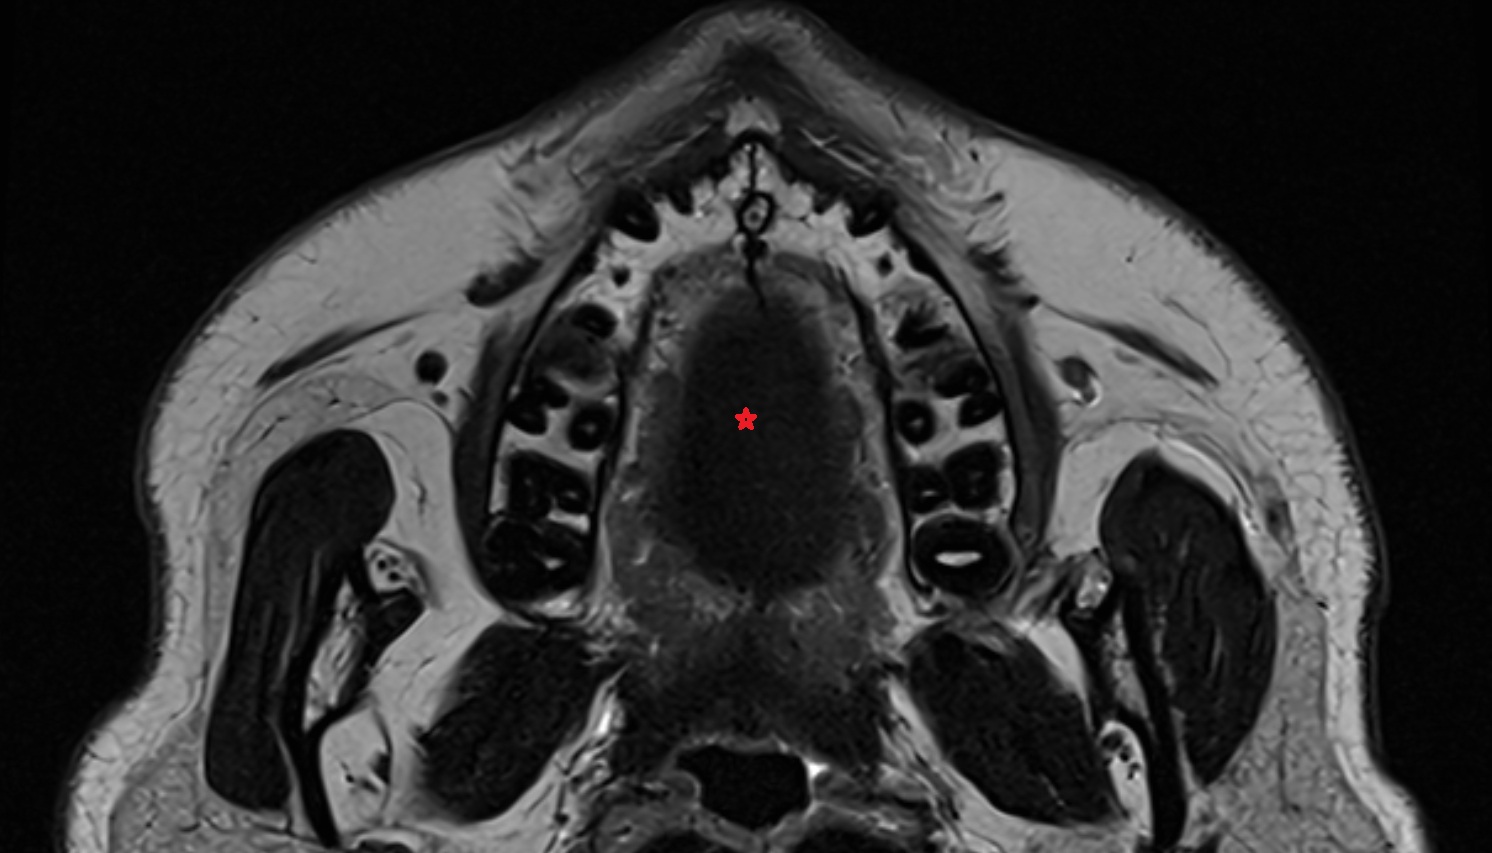

- Masseter muscle (Superficial part)

- Superficial head of medial pterygoid muscle

- Lateral pterygoid muscle

- Medial pterygoid muscle

- Temporalis muscle